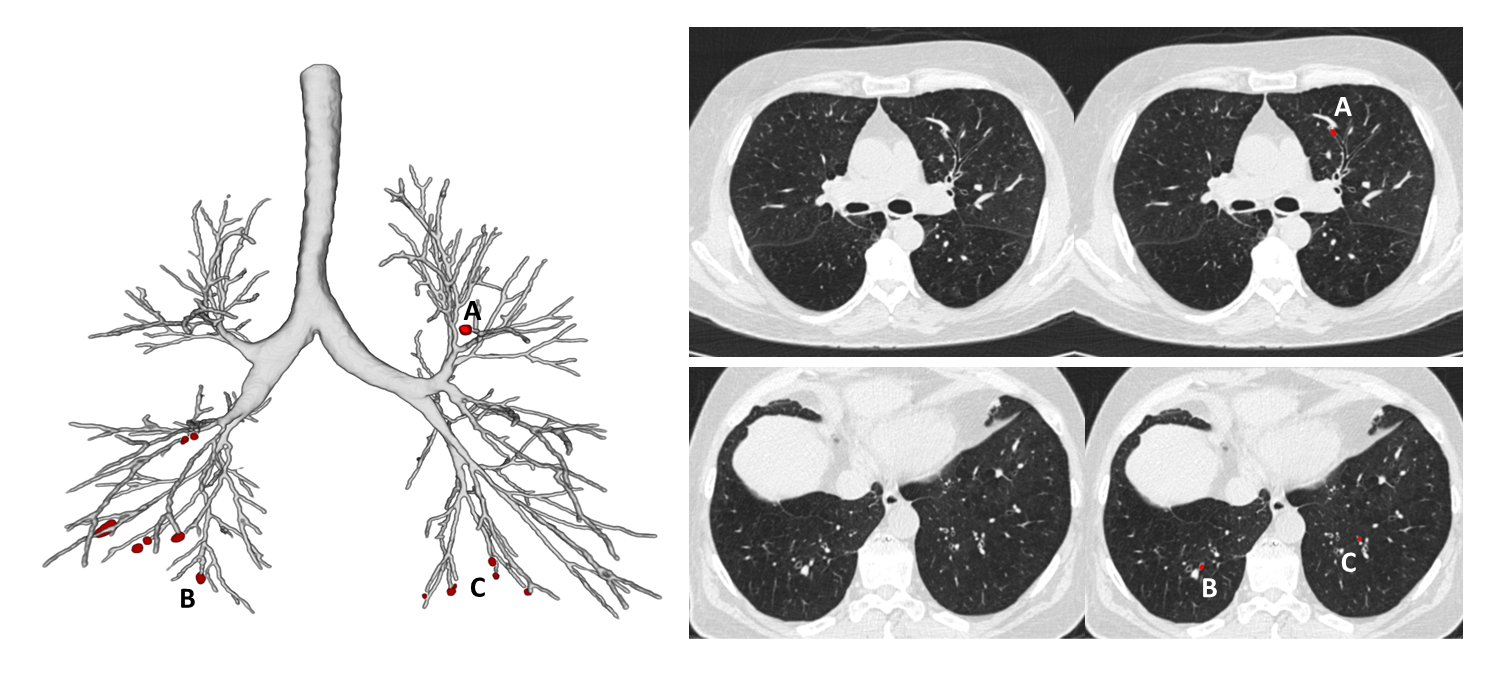

Figure 1

Mucus plug identification from chest CT

With the precision and robustness that deep learning technology brings to the table, we can recognize and precisely quantify details that could not be detected before. We are now able to look deep into the entire bronchial tree, and measure all relevant airway dimensions up to the smallest bronchi. This allows us to obtain objective, accurate, and sensitive information of all the bronchi visible in the scan in a matter of minutes. In addition, AI algorithms are much faster and more precise in detecting, localizing and counting mucus plugs (Figure 1).